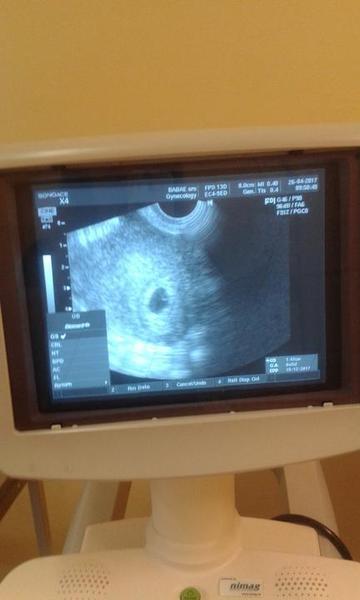

@kudusko prikladam obrazok prveho sona kde je ambulancia lekara a je vidno ze lekar robil aj merania

@archanjel007 to sono vyzerá v pohode, vidím zltkovy vak dokonca,na 6+5 krásne. To bolo 26.4. dnes by mala byť tých 9+4. Ale o 2tt dnes menšie????? Ja tomuto nerozumiem